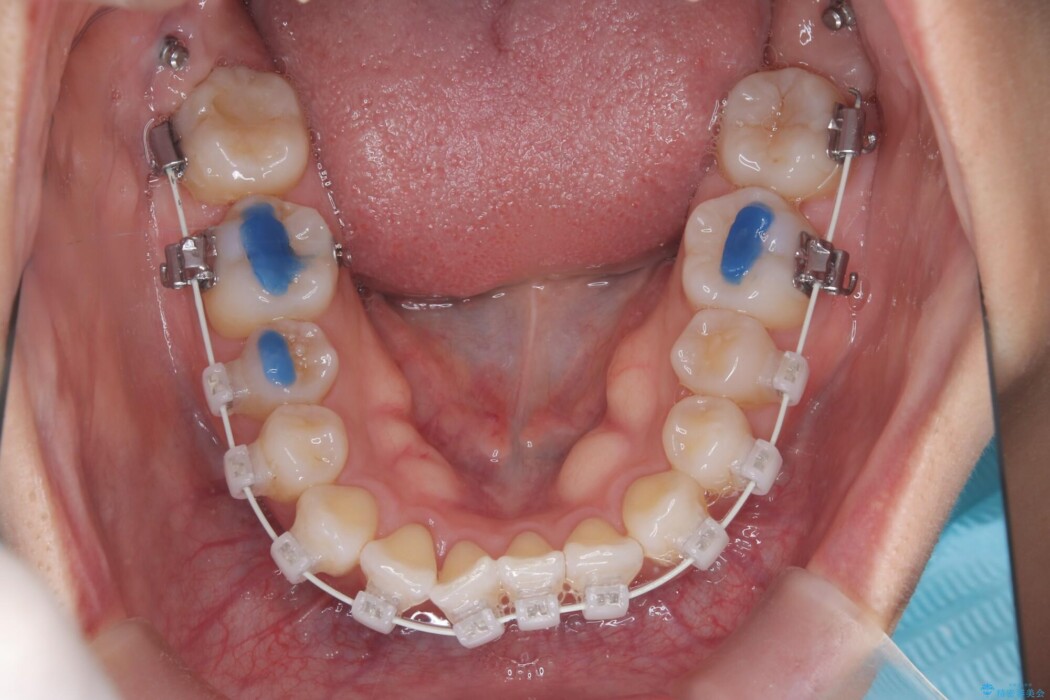

治療概要

- 矯正装置:ワイヤー(審美装置)

上下のガタつきと、右上の奥歯が外側に飛び出して上下が正しく噛み合わないシザーズバイトの改善のためにご来院された患者様です。

矯正検査の結果、右上7番が頬側に大きくズレており、うまくかみ合っていない状態でした。

全体的にスペース不足ではありましたが、患者様は抜歯をしたくないとのご要望だったため、上顎の裏側に「トランスパラタルアーチ(TPA)」という装置を装着し、奥歯の幅を調整しながらスペースを確保する計画を立案。

矯正装置は目立ちにくい審美ワイヤーを使用しています。